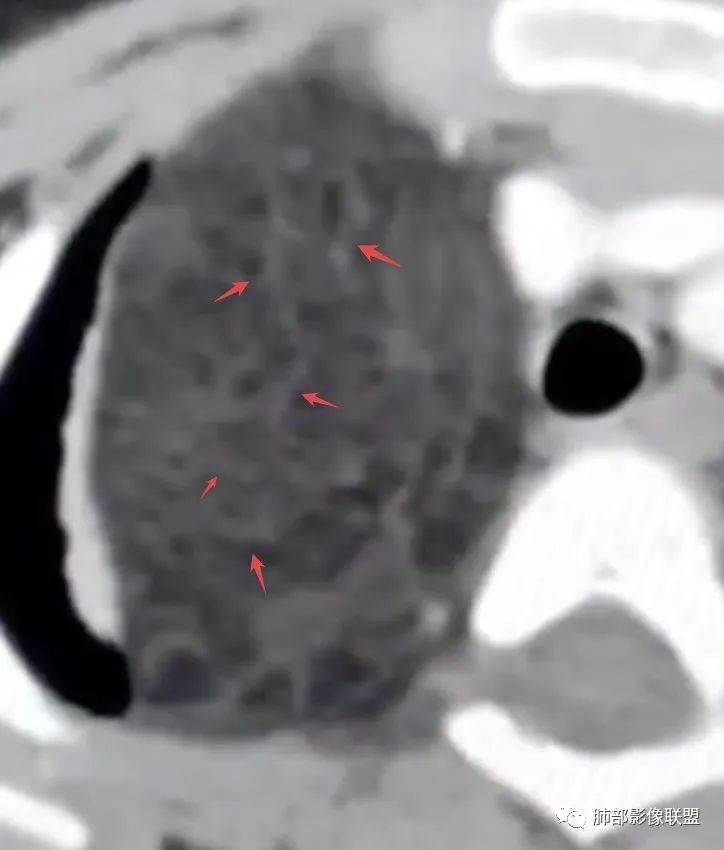

6.影像学表现:

脂肪母细胞瘤由成熟程度不同的脂肪组织、纤维间隔、黏液基质、小血管丛等间质成分组成,以脂肪组织与黏液样基质为主,其影像学表现取决于上述组织成分。典型的CT和MRI表现为:前后纵隔均可发生,常见于前纵隔;肿块大小不一,直径多在3cm~7cm,密度均匀,CT值呈水样或脂肪密度,脂肪组织密度或信号为主的肿块,其内密度或信号不均匀,可见粗细不一的分隔影,且有结节、片状影,后者可呈轻中度强化;结节状肿瘤包膜完整;弥漫性者包膜不明显,常呈浸润性生长;周围结构为受压和推移改变,可有少量胸腔积液,淋巴结无增大。